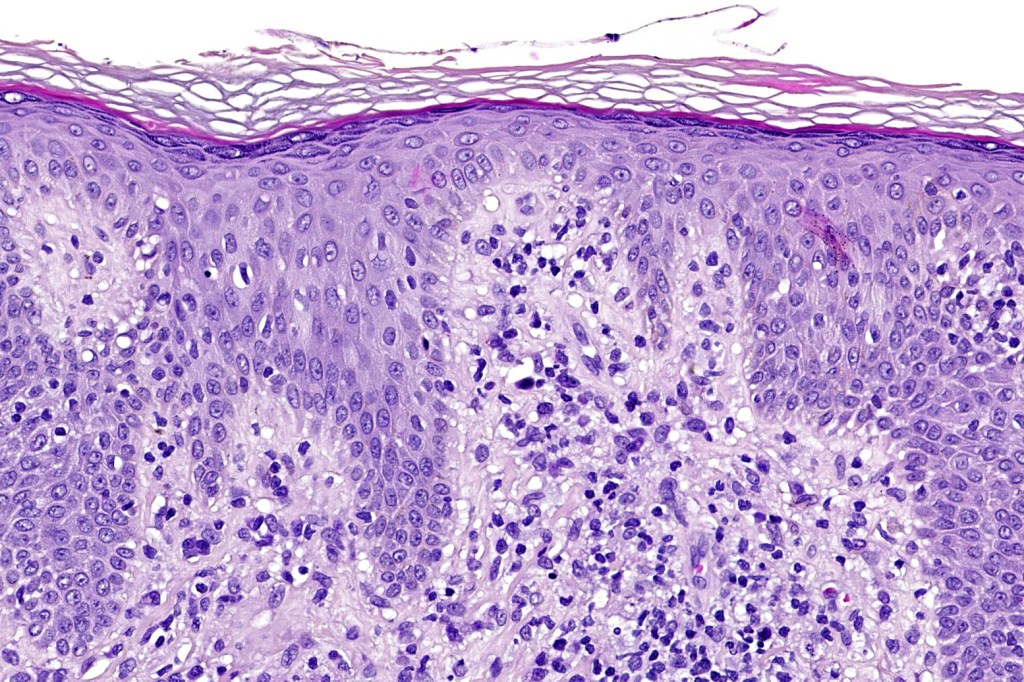

Histological features

The histological hallmark of mycosis fungoides is the presence of large atypical lymphocytes with a convoluted/cerebriform nuclear border (Sézary cells). These may be found at the epidermal-dermal jnuction and as collections within the epidermis (Pautrier microabscess). These are most easily found in plaque stage disease. The epidermal component can be subtle in patch stage disease and is often lost in tumor stage dsease. The classification into patch, plaque & tumor stage disease is less helpful histologically as the features merge from one to the other. It is all a matter of degree.

Patch stage disease

•Changes can be subtle & dependent on clinicopathological correlation; in many patients sequential biopsies over many months may be necessary to establish the diagnosis.

•Mild hyperkeratosis & focal parakeratosis, acanthosis, epidermal atrophy or of normal thickness

•Superficial dermal lymphocytic infiltrate containing variable numbers of Sézary cells with atypical, irregular, hyperchromatic nuclei surrounded by a halo; these can be very few in number and dependant on viewing multiple levels

•Palisading of atypical lymphocytes along the epidermal-dermal border

•Pautrier microabscesses may be present but are often absent in patch stage disease

•Variable interface change with keratinocyte necrosis & pigmentary incontinence